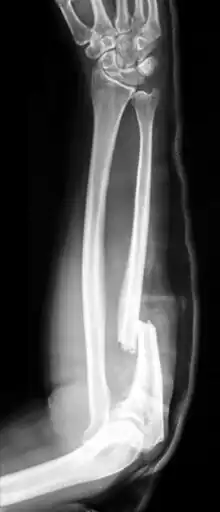

An ulna fracture is a break in the ulna bone, one of the two bones in the forearm.[2] It is often associated with a fracture of the other forearm bone, the radius.[1][3]

Fractures of the ulna can occur at different levels of the bone: near the wrist, in the middle or near the elbow.[2] The fracture may be confined to the ulna or accompanied with damage to the radius or the wrist or elbow joints.[2]